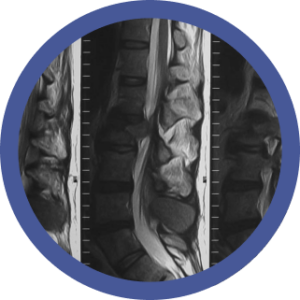

El diagnóstico por imagen del sistema nervioso central es una disciplina en constante evolución y de vital importancia para la práctica clínica. Por lo cual el conocimiento de una amplia variedad de patologías, desde tumores hasta accidentes cerebrovasculares, traumatismos craneoencefálicos y enfermedades neurodegenerativas, nos brinda habilidades para nuestra actividad laboral diaria.

La neuroimagen, como herramienta diagnóstica y de investigación, ha revolucionado nuestra comprensión del cerebro humano. Su aplicación en la práctica clínica ha permitido un diagnóstico más preciso y temprano de una amplia gama de enfermedades neurológicas, mejorando significativamente la atención al paciente.

Por otro lado, la evolución de las tecnologías de neuroimagen (RM, TC, PET, IA) ha ampliado considerablemente sus aplicaciones clínicas y de investigación. Así como también, la demanda de profesionales capacitados en neuroimagen ha aumentado considerablemente y que posean una formación sólida en los principios físicos, la anatomía, la fisiología y la patología del sistema nervioso central.